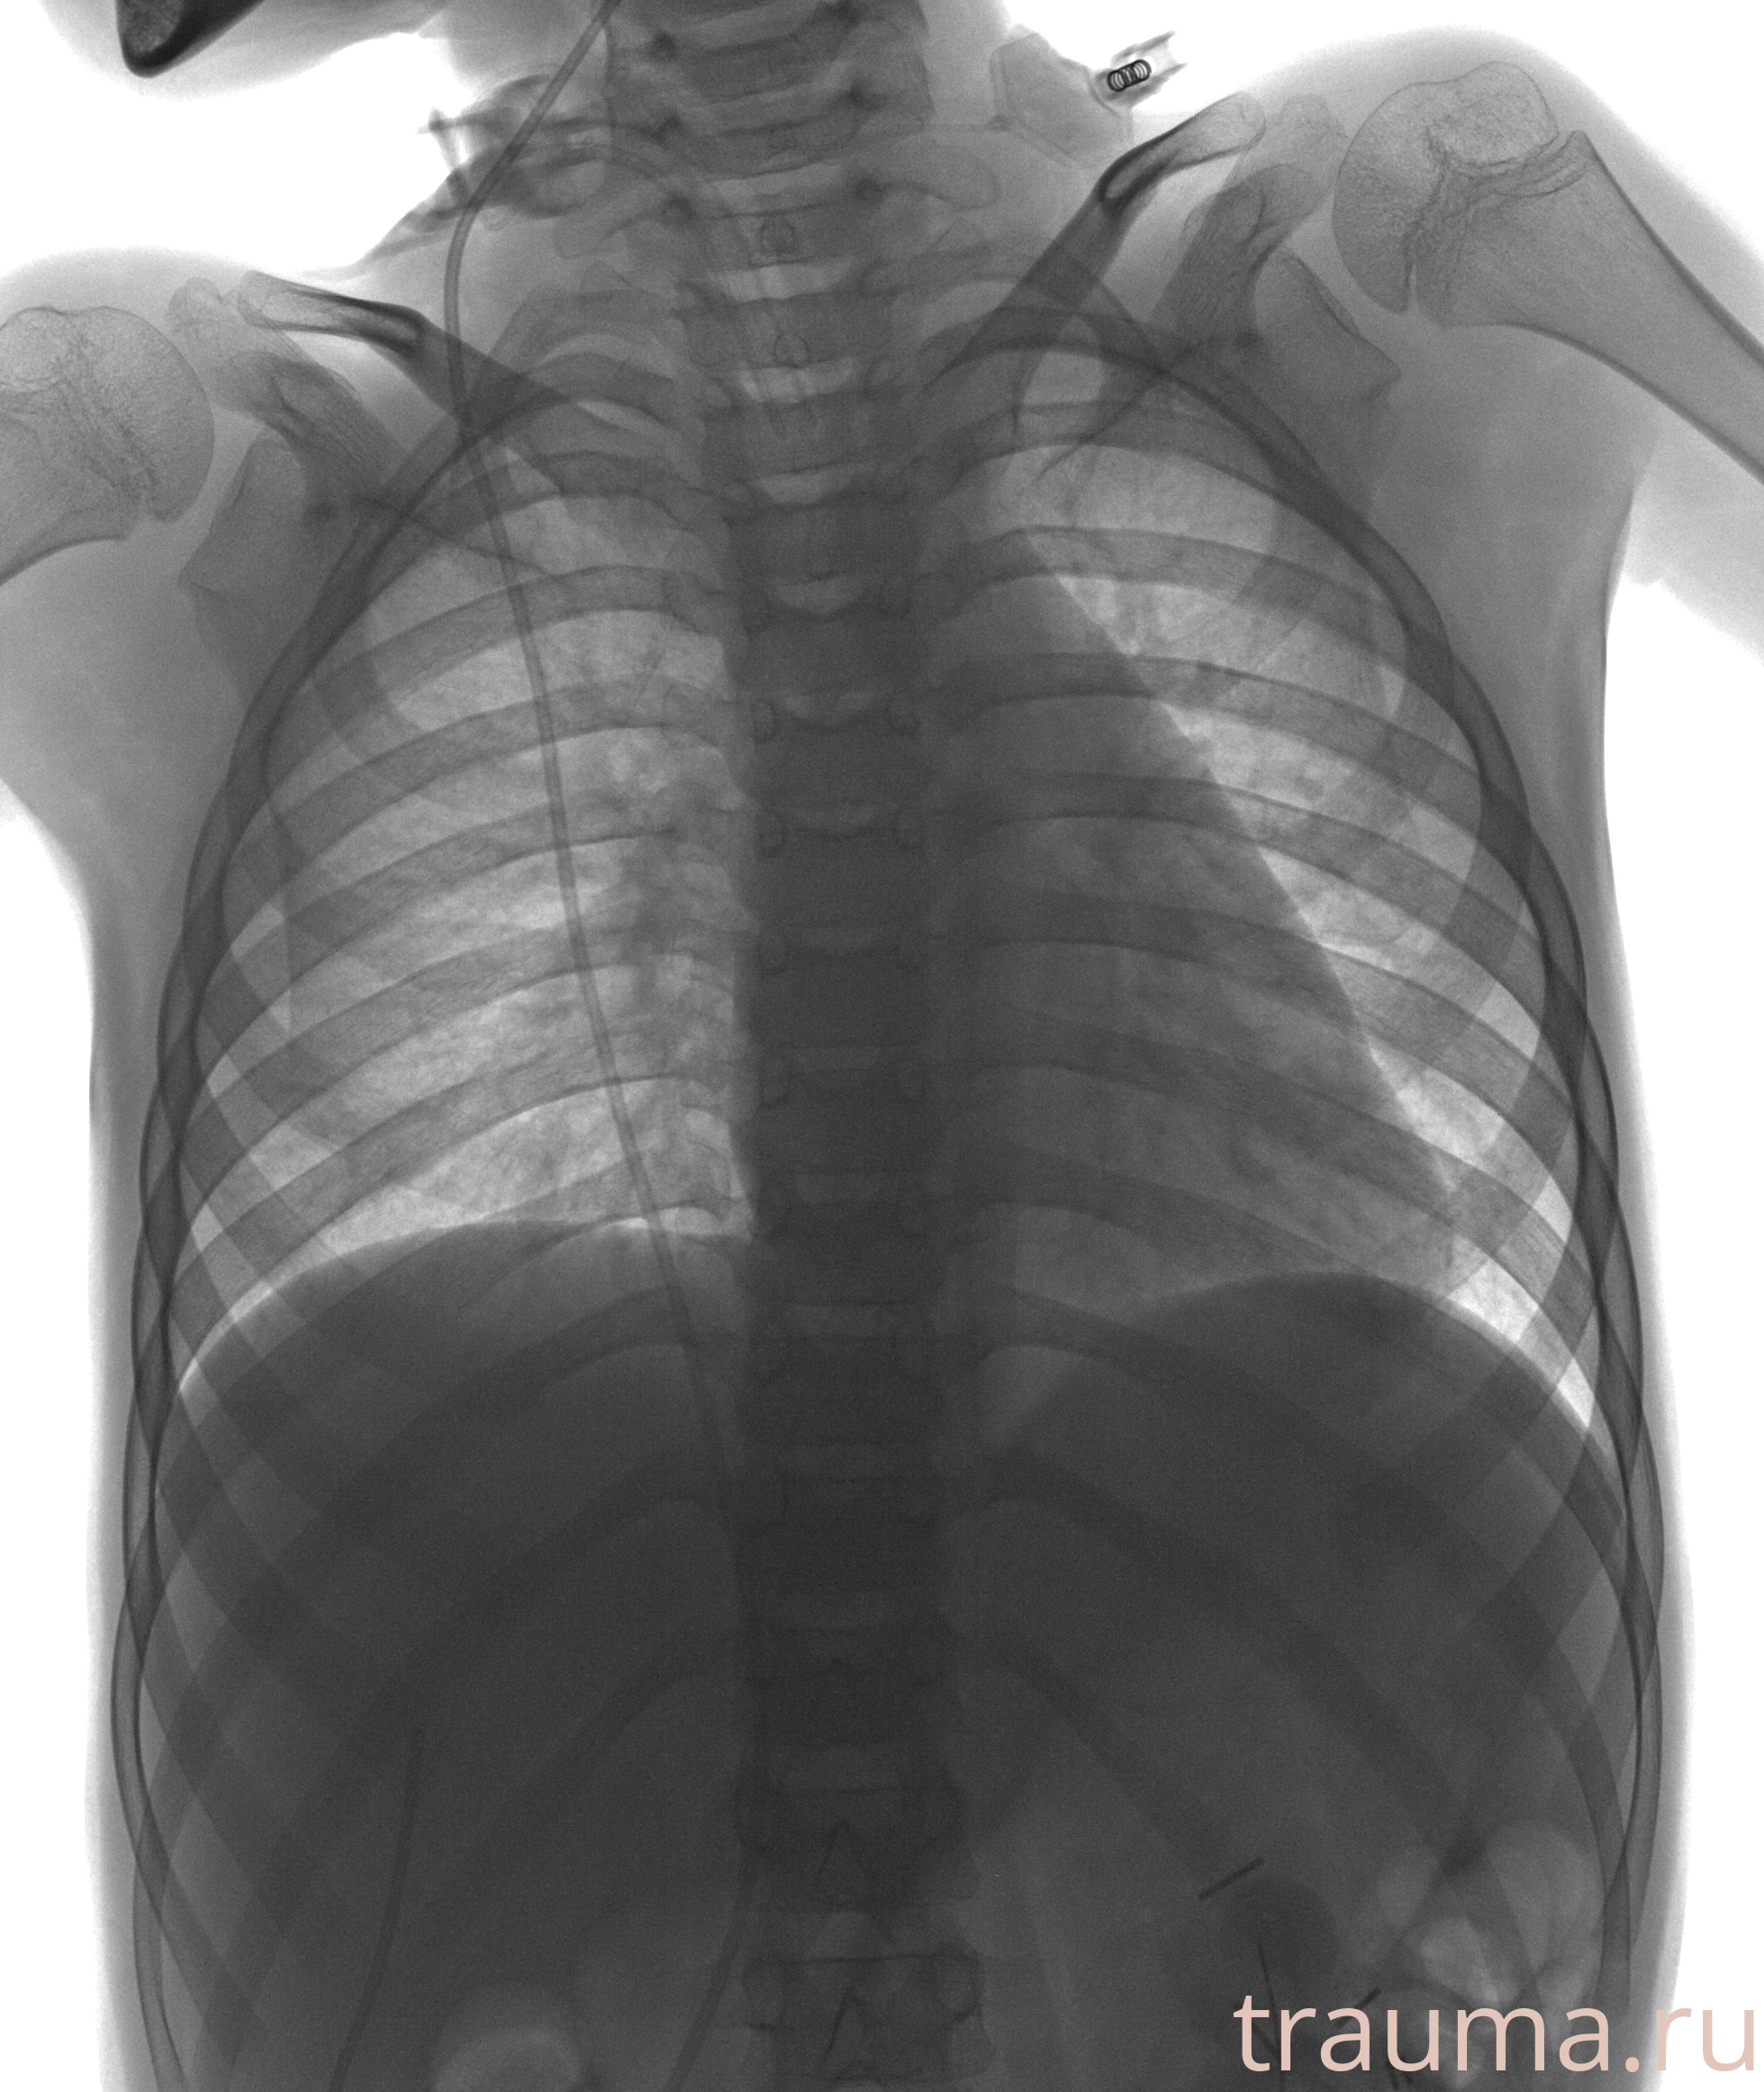

Рентгенограммы

Рентген на дому: по вашему адресу приезжает врач-рентгенолог, травматолог-ортопед с мобильным рентгеновским аппаратом, проводит диагностику травмы или заболевания, делает необходимые рентгенограммы, дает рекомендации по дальнейшему лечению. Получить качественные снимки в домашних условиях возможно благодаря уникальной методике, разработанной МосРентген Центром для института  Склифосовского

Яркость: 1   Контраст: 1   Инвертировать: 0 Увеличение: 1

Перетаскивайте мышь вверх/вниз для контраста, влево/право для яркости. Прокрутка колесом изменяет масштаб. Нажмите Сбросить для возврата к исходному изображению. При увеличении держите мышь в той области, которую хотите рассмотреть.